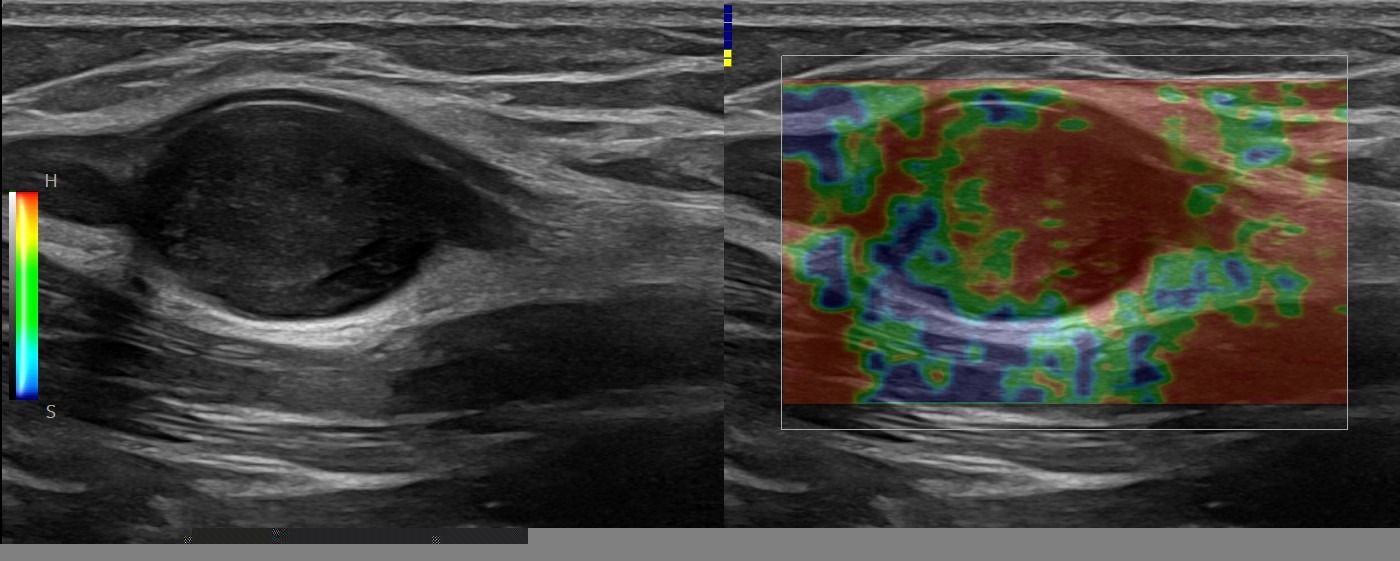

- Focal Lesions (tumors, neuromas)